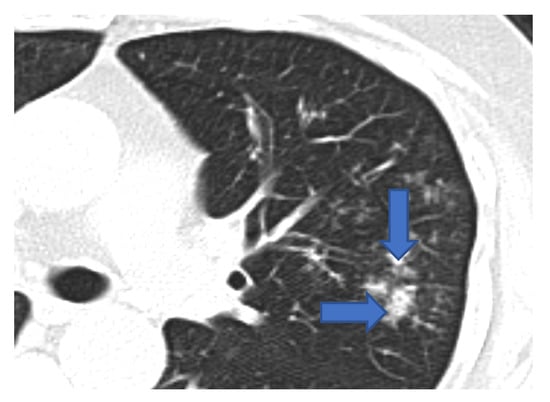

5.1. Role of Diagnostic Imaging

Diagnostic imaging is vital for early detection of invasive mucormycosis in patients with clinical suspicion. Certain distinguishing features of the lung parenchyma on a CT scan of the chest in patients with PM include multiple pulmonary nodules, often pleural-based, presence of lung cavitations and effusions (Figure 1, Figure 2, Figure 3 and Figure 4) [23]. The ‘reverse halo sign’ (central ground glass opacity surrounded by dense consolidation) is highly appreciated, mainly in neutropenic leukemic hosts. In a recent systematic review of CT findings in 16 patients with proven CAPM, consolidation and cavitation were seen in 11 (69%) patients, pleural effusion in 7 (47%), pneumothorax and nodules in 3 (19%) and ‘reverse halo sign’ and pulmonary embolism was seen in 2 (13%) patients [24]. Previously, Nam et al. reported that in hematologic patients, while consolidation and nodules are seen earlier in the disease process, central necrosis, cavitation and the air crescent sign are late findings [25]. This would suggest that CAPM is either under-diagnosed due to lack of differentiation from other fungal, including aspergillosis or bacterial pneumonias, or is diagnosed much later in the illness.

Figure 2. CT scan of the same patient showing a pleural-based consolidation with central clearing (blue arrow) and surrounding, denser, consolidation typical of reverse halo sign; also seen in left mild pleural effusion.